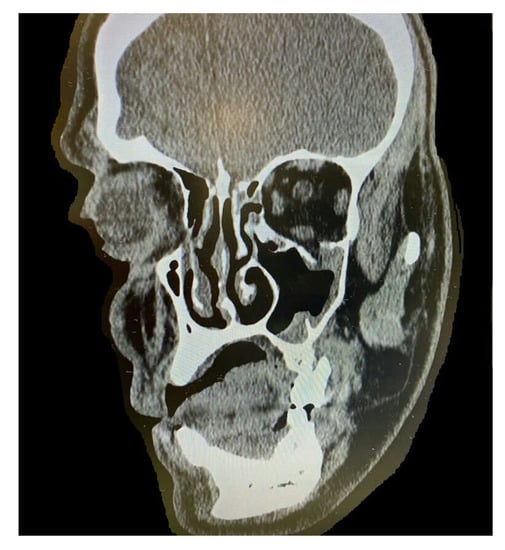

By counting the occurrence of the sites of fracture, either alone or combined, we found that the orbital floor (n = 52, 41.9%; Figure 1) and lateral wall (n = 31, 25.0%) were the most prevalent sites of bone fracture among the study patients (Figure 2, Figure 3 and Figure 4). Figure 5 illustrates the distribution of the causes of trauma.

Figure 4.

Orbital floor fracture with entrapment of the inferior rectus muscle; patients present with vertical gaze diplopia and restriction of upgaze.